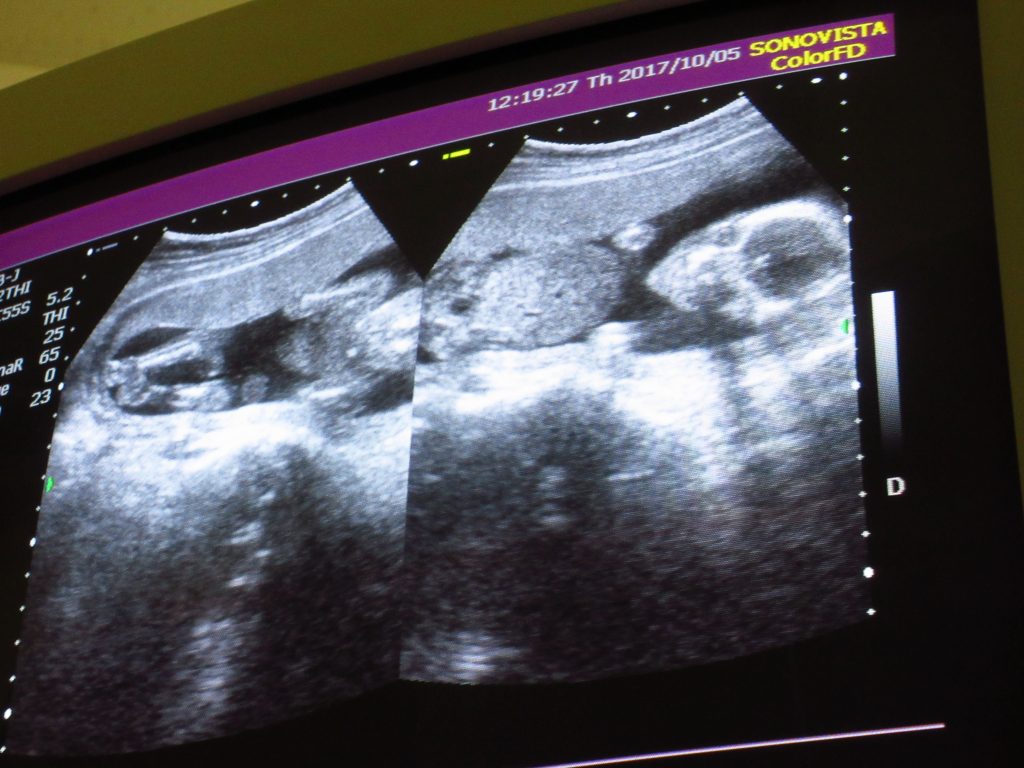

10月。戌の日に、水天宮の安産祈願のお参りに行った。

11月。性別も女の子だと分かった。

12月。あっというまに妊娠中期が終わり、後期に入る。

おなかが大きくなったり、動悸だったり、電車がきつかったり、

身体の変化にはいつも戸惑いを隠せないけど、ちゃんと育ってくれている証拠だ。